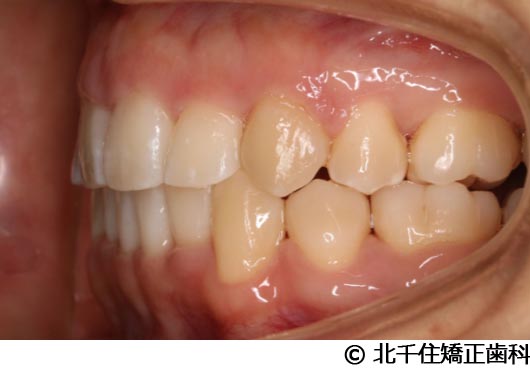

【症例2】上顎前突症

- 治療前

- 治療中

- 治療後

- 治療名

- 上顎前突症

- 費用

- 1,399,000円(税込)

- 期間

- 3年6ヵ月

- 治療回数

- 42回

- 通院頻度

- 1ヵ月ごと

- 年齢・性別

- 19歳10ヵ月・男性(初診時)

主訴:出っ歯、口元の突出、横顔をきれいにしたい

骨格性の上顎前突、上下顎第一小臼歯4本及び上顎第二大臼歯を抜歯して矯正用アンカースクリューを併用してワイヤー矯正治療(セラミックブラケット)。

骨格性上顎前突に対し、抜歯および矯正用アンカースクリューを併用した矯正治療により歯列および咬合関係の調整を行った症例である。治療後は保定装置を使用し、歯列および咬合の安定維持を目的として定期的な経過観察を行っている。

※治療結果は個人差があります。

治療を行う上での注意点(リスク・副作用)

歯磨き不良に伴うカリエスや歯周病、顎関節症、歯根吸収など。